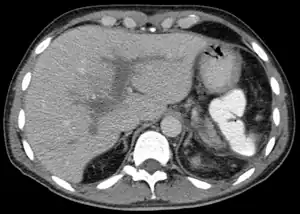

Portal vein thrombosis seen with computed tomography.

The diagnosis of portal vein thrombosis is usually made with imaging confirming a clot in the portal vein; ultrasound is the least invasive method and the addition of Doppler technique shows a filling defect in blood flow. PVT may be classified as either occlusive or nonocclusive based on evidence of blood flow around the clot.[5] An alternative characterization based on site can be made: Type 1 is limited to the main portal vein, Type 2 involves only a portal vein branch (2a, or 2b if both branches are affected), and Type 3 if clot is found throughout both areas.[8] Determination of condition severity may be derived via computed tomography (CT) with contrast, magnetic resonance imaging (MRI), or MR angiography (MRA). Those with chronic PVT may undergo upper endoscopy (esophagogastroduodenoscopy, EGD) to evaluate the presence of concurrent dilated veins (varices) in the stomach or esophagus.[3] Other than perhaps slightly elevated transaminases, laboratory tests to evaluate liver function are typically normal.[1] D-dimer levels in the blood may be elevated as a result of fibrin breakdown.